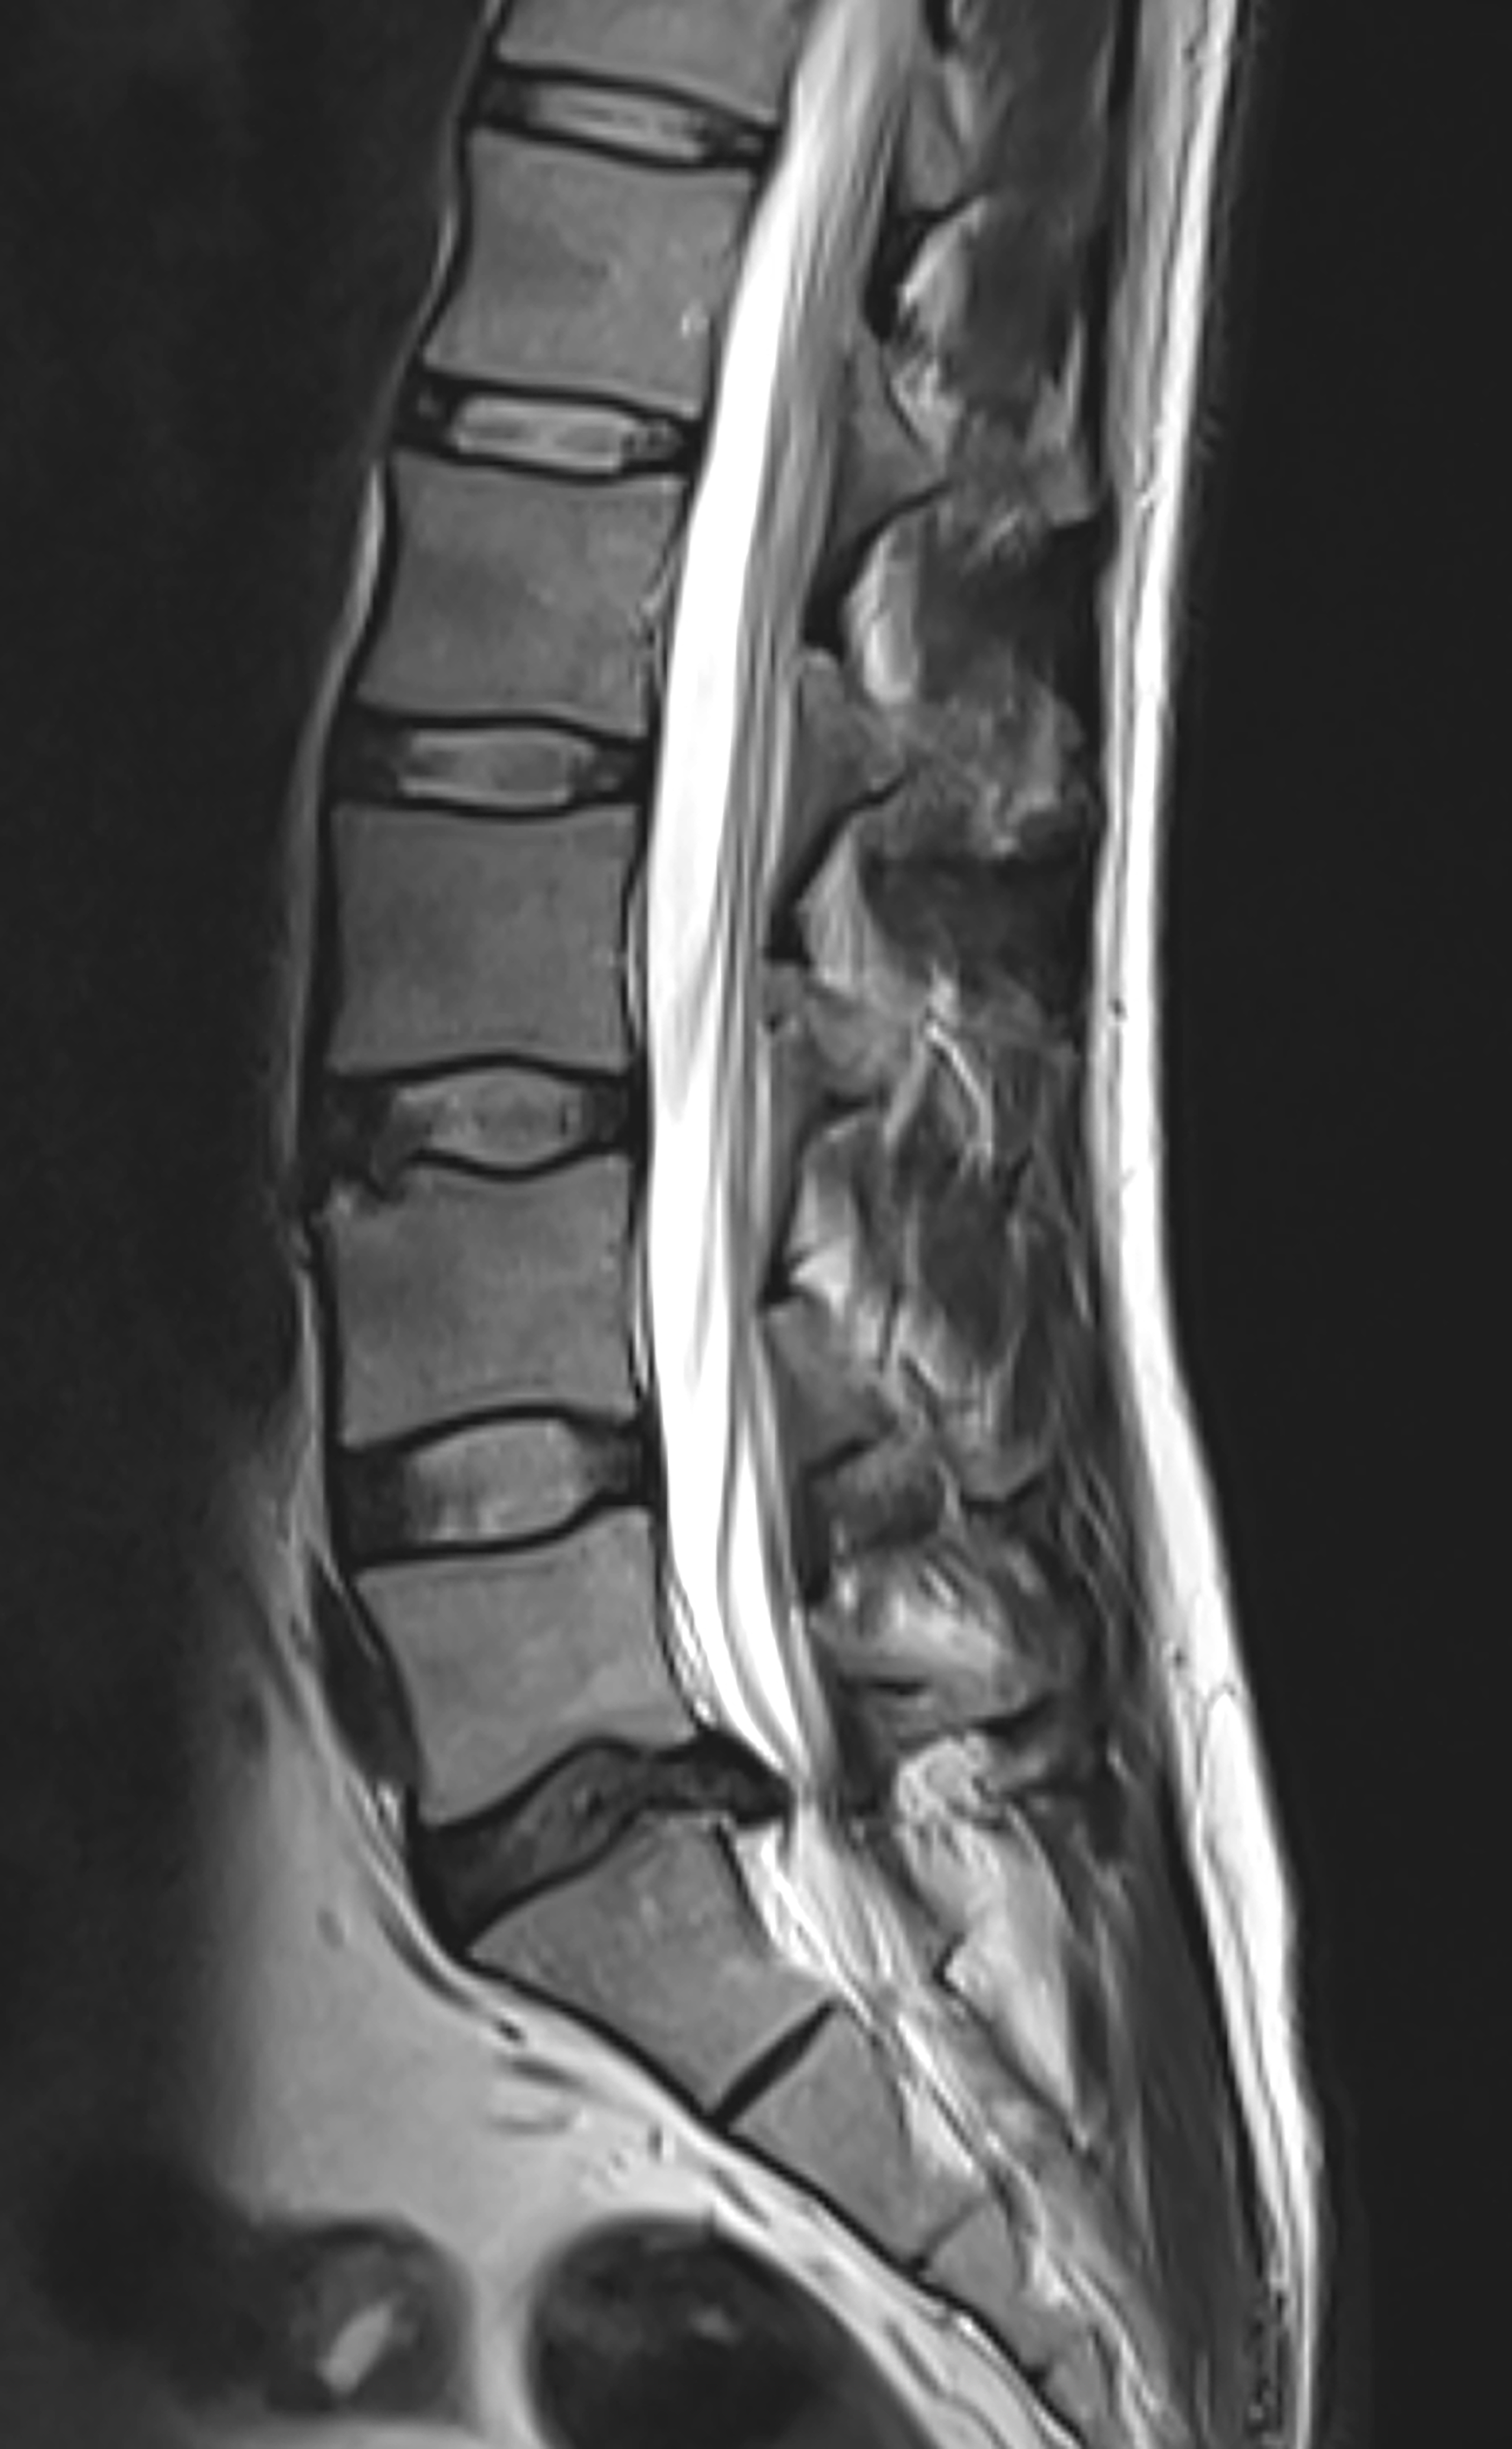

For patients with back or leg pain, the source can usually be traced to nerve pressure, such as a herniated disc in younger patients or arthritic bone spurs in older populations. Traditionally, this would leave them to choose between undergoing extensive surgery to correct the issue or continuing treatments to mitigate the pain indefinitely. At UT Southwestern, patients now have a much less invasive option in endoscopic spine surgery, an outpatient procedure to fix the underlying issue and relieve pain.

The procedure involves making a small incision in a patient’s back where the issue is located and inserting an endoscope, a thin tube with a camera at the end. The surgeon uses this tube as a channel for any instruments needed to treat the problem, while also monitoring the area in real time with the camera. Afterward, the incision can be closed and covered with a small bandage and, because this procedure requires the least amount of tissue damage, patients can see results right away and often only need to take pain medication for a day or two. Patients are usually released the same day to a friend or family member who can take them home – just like with injections. From a patient’s perspective, the only difference between injections and endoscopic surgery is recovering from general anesthesia, which typically takes a few hours.